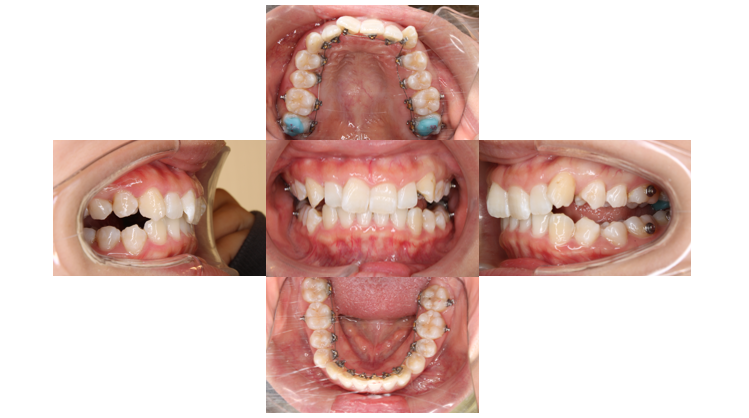

装置装着後

上下裏側に装置がつきました

下の歯と装置が当たる場所があるので青い材料を歯に盛り、当たらないようにしています